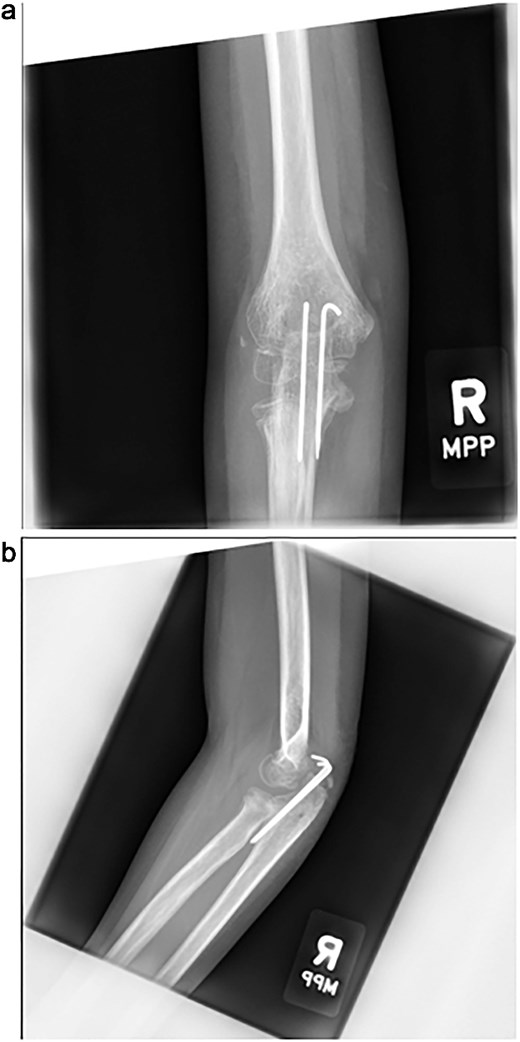

The cast was removed at 5 weeks, and radiographs confirmed maintained alignment (Fig. 4a and b), allowing the patient to transition to a hinged elbow brace. Four months after surgery, she underwent planned removal of the Kirschner wires and tension band (Fig. 5a and b). At 6 months, elbow range of motion was 10°–130° on the right, compared to 0°–140° on the left, and she reported no pain with activities. She was subsequently lost to follow-up.

(a, b) Radiographs at 5 weeks, showing maintained alignment at the time of cast removal.

(a, b) Intraoperative fluoroscopic images following hardware removal at 4 months, demonstrating restoration of joint congruity.